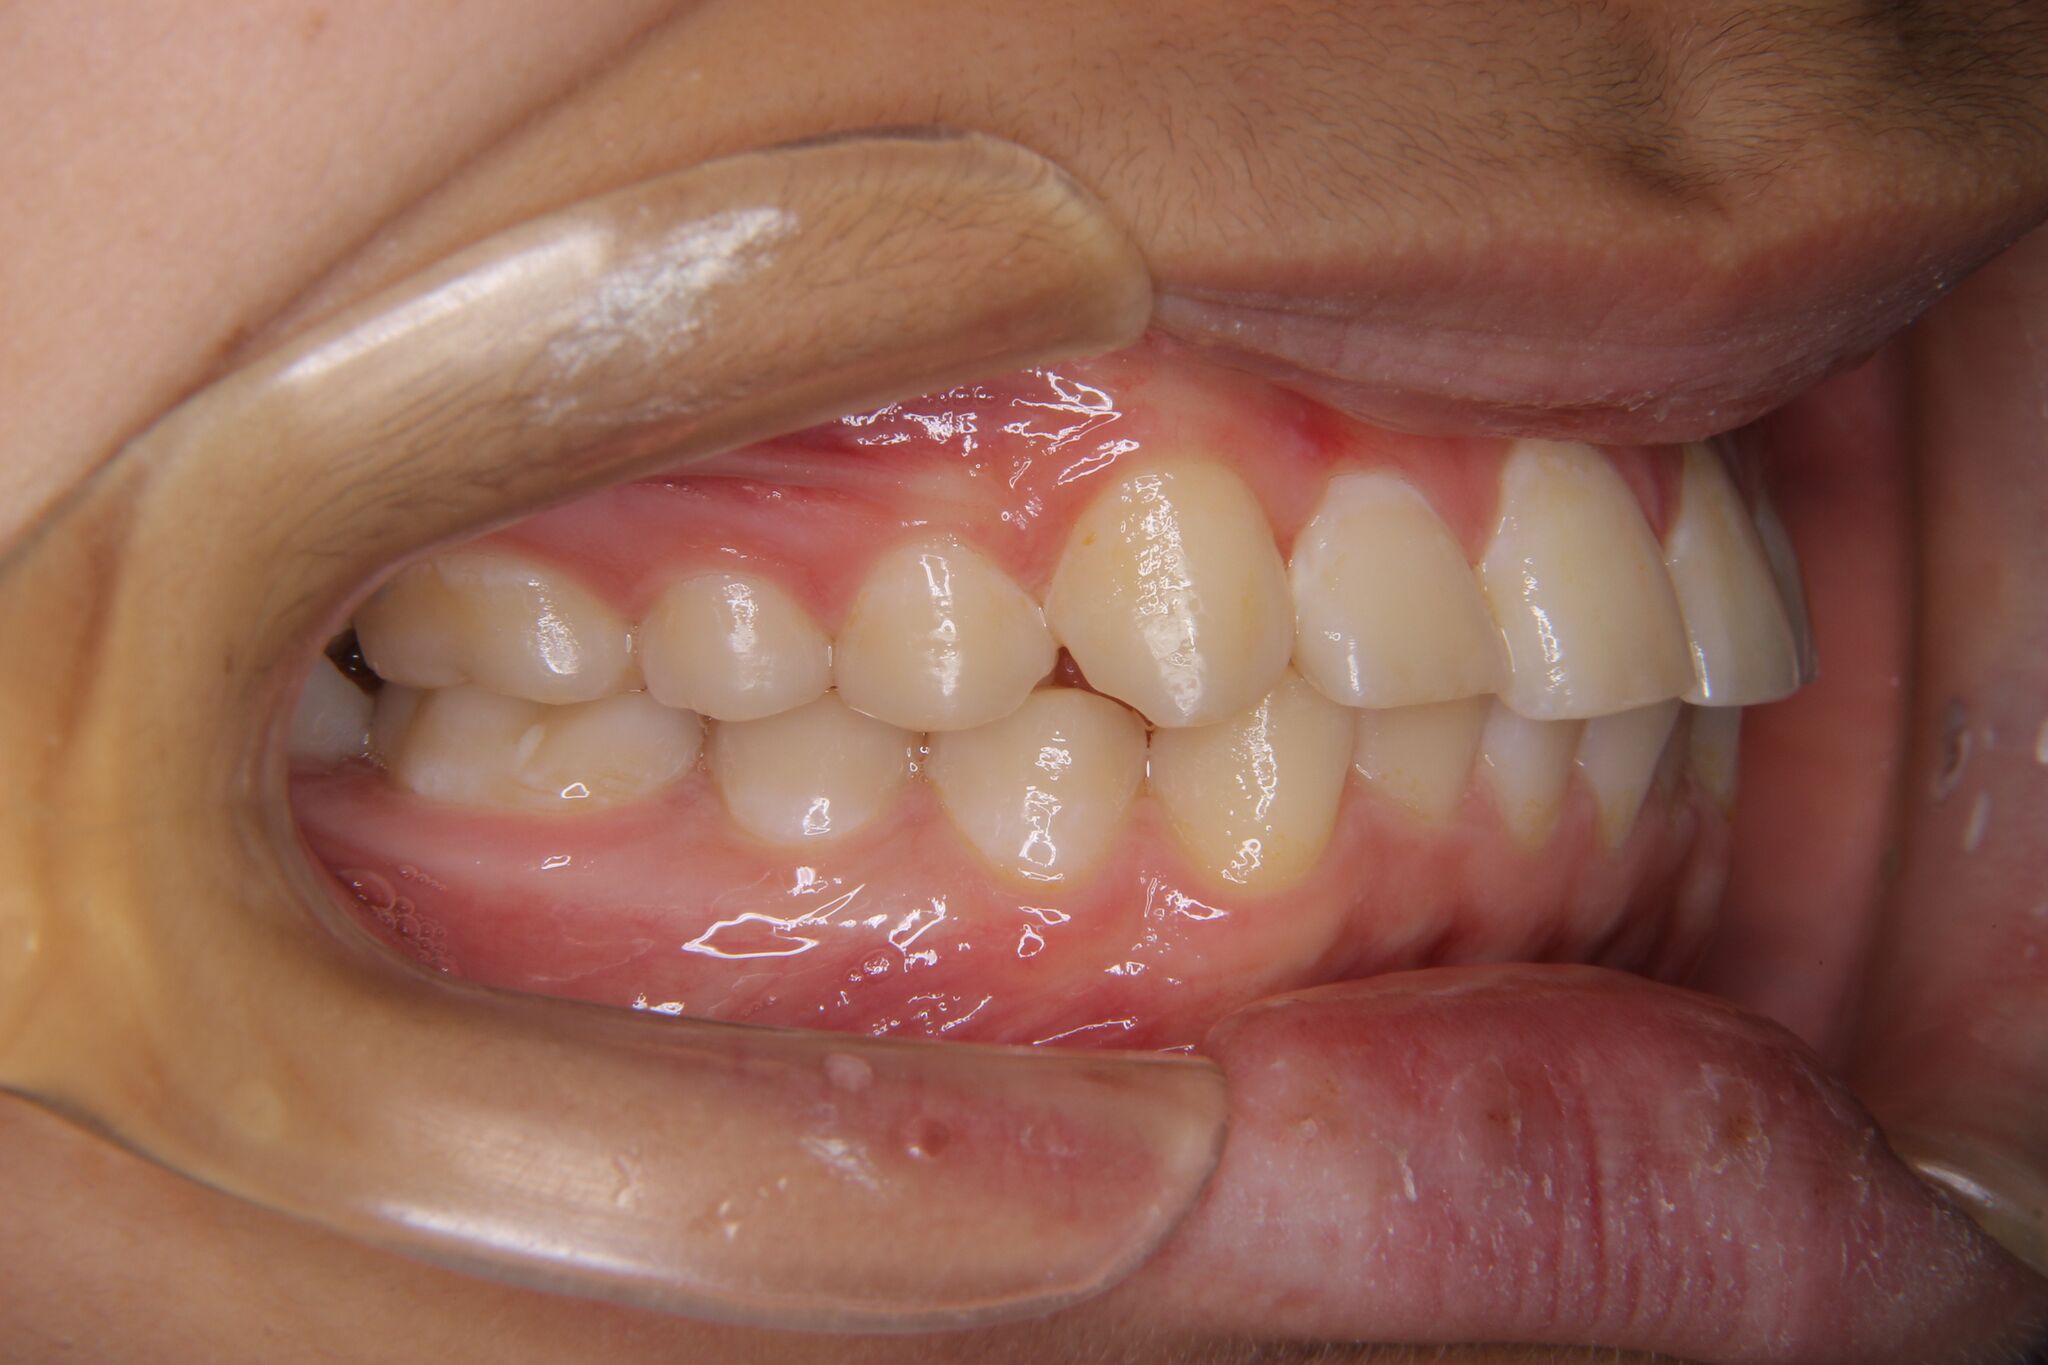

【小学生男子】深い噛み合わせ・上顎の犬歯スペース不足の矯正歯科治療

噛み合わせが深く、上下奥歯の関係のズレがみられました。

その後、ワイヤーをセットし、犬歯を下ろしてきました。

現在、全ての歯の萌出まで、経過を見ています。

全部の永久歯が萌出後、ワイヤーかインビザラインにて、きちんと

した噛み合わせを作っていきます。